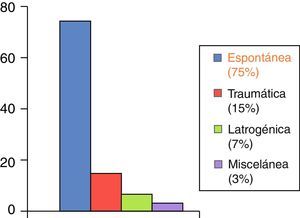

Su etiología es variable: espontánea, traumática, iatrogénica. A día de hoy la más frecuente es de origen idiopático o espontáneo (fig. 3). La clínica es poco específica, pero conjuntamente con los factores de riesgo nos ayudará ante la sospecha de dicho cuadro. Así puede cursar con: dolor abdominal y/o torácico, cuadros isquémicos a diferente niveles, y en un porcentaje nada desdeñable, el cuadro clínico es asintomático (17%)2 (fig. 4). El diagnóstico de confirmación se realiza en más de la mitad de los casos mediante angio-TAC (75%), aunque también se puede realizar a través de estudios ecográficos, angiográficos o con angio-RM5.